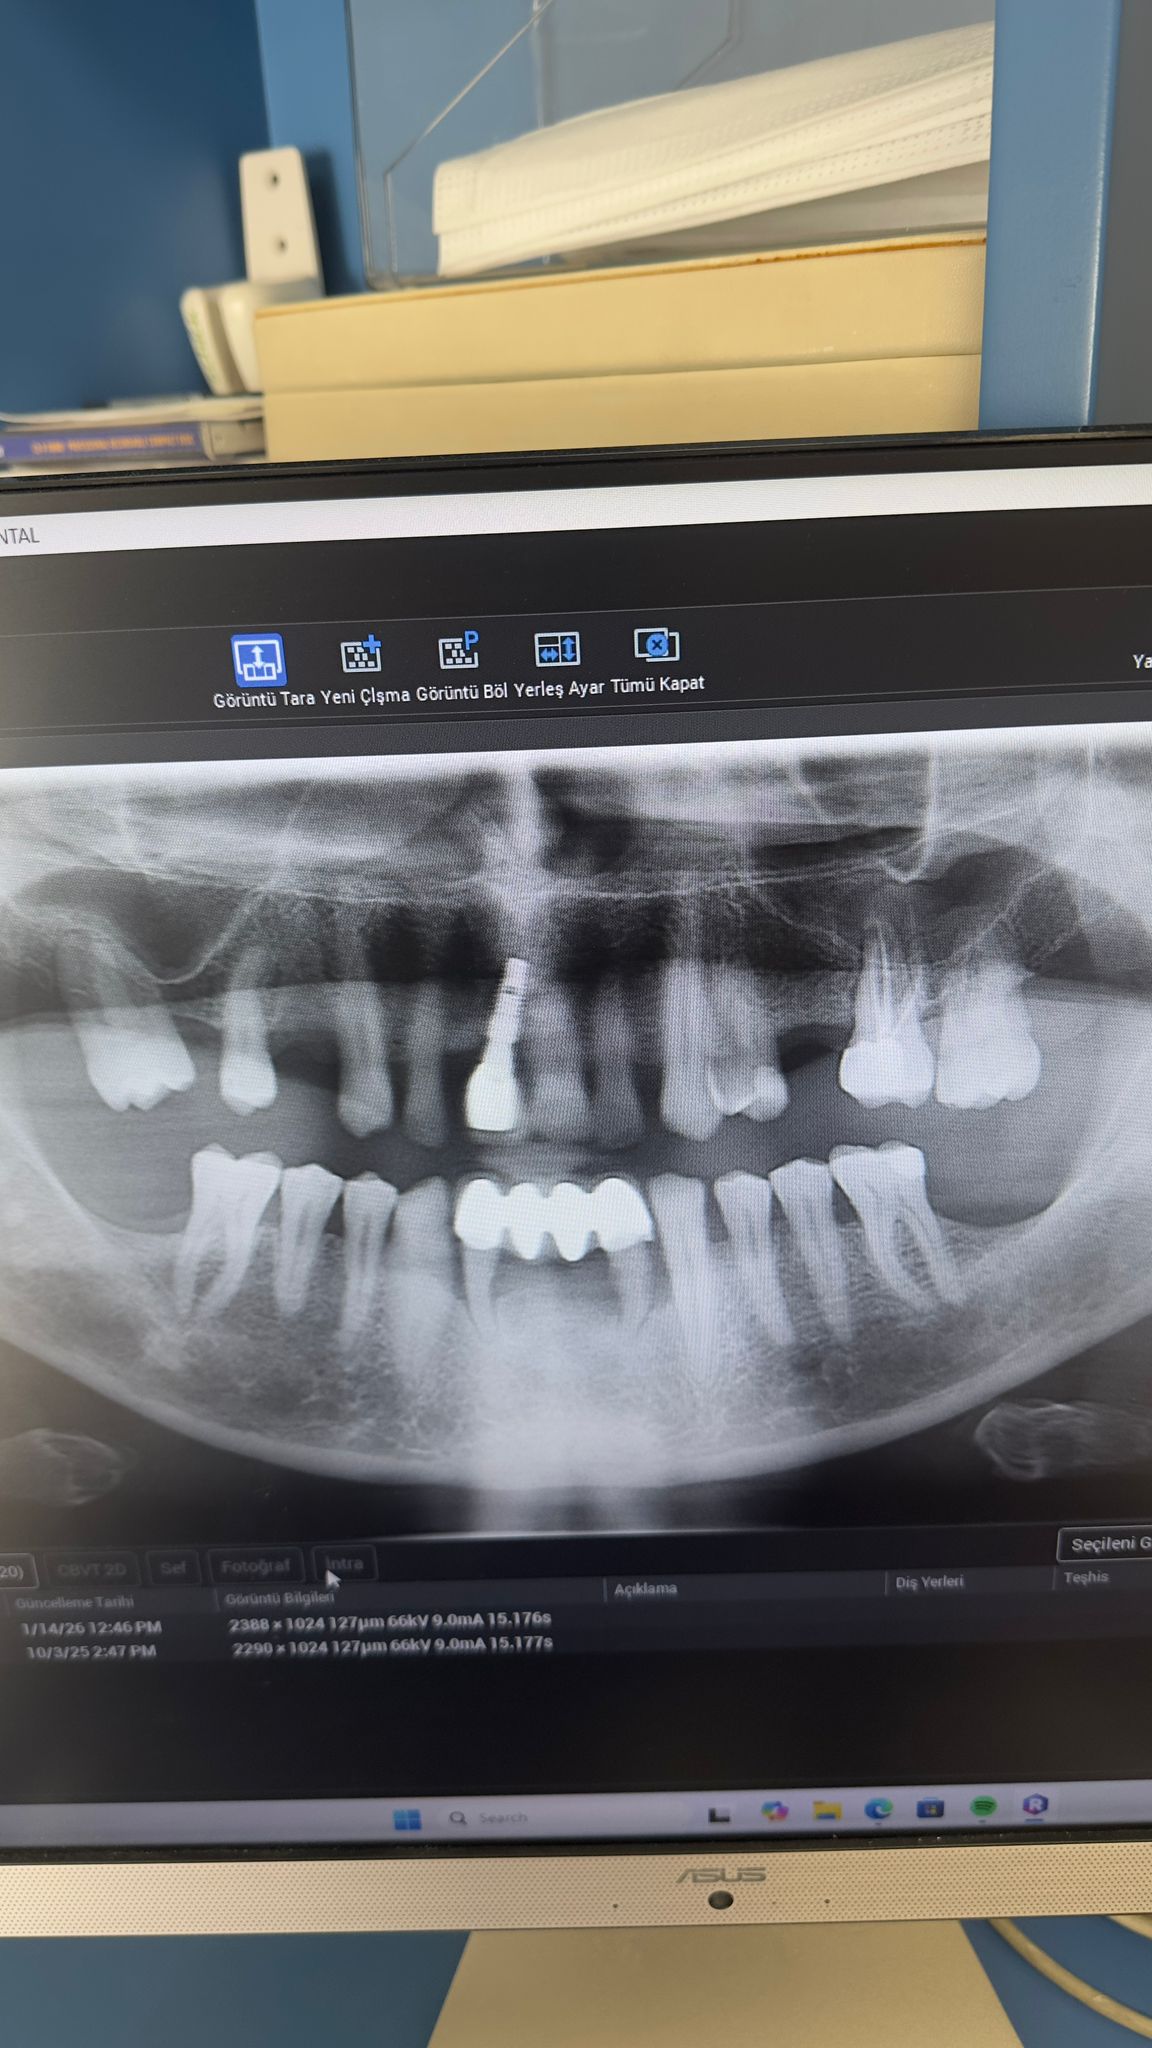

Nesrin Bat ( 01.02.1993) Muayene sonrası alt sağ 1. büyük azı dişinin eksik olduğu tesbit edilmiştir. Gerekli tetkikler sonrasında 3.7 mm çapında bir implant yerleştilmiştir. Osteointegrasyon için beklenmektedir. 29 Eylül Muayene 13 Ocak implant yerleştirildi.